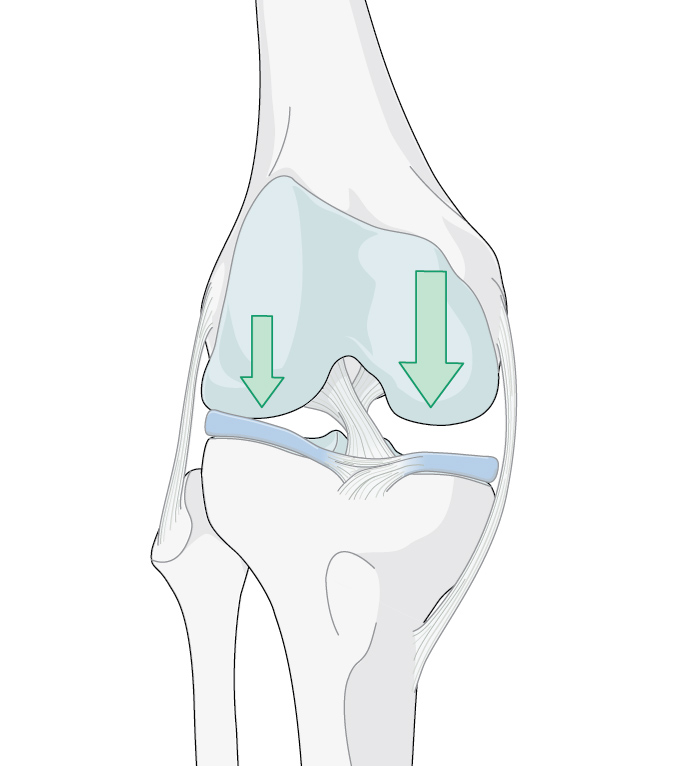

Each step you take sends forces that amount to three to eight times your body weight between your femur and tibia, through your knee [1]. Considering this, it is no wonder that the most common type of arthritis is osteoarthritis (OA) of the knee [2]. It is associated with “wear and tear”, injury, and genetic predisposition, and is more likely to occur in people over 50 years old (although younger individuals can also have OA) [3]. Surgical treatment options are available that aim to support improved mobility, reduce pain, and facilitate active lives, including sports—which is a priority, especially for many younger people with knee OA.

Since 1958, when the procedure was first performed by Jackson [6], and popularized by Coventry [7] starting in the 1960s [8], HTO has been used to treat unicompartmental OA in knees. Whereas UKA and TKA replace elements of the knee joint with prostheses, either in part or in full, respectively, HTO takes a biomechanical approach and is viewed as a realignment procedure. “HTO does not replace the knee joint but optimizes the joint biomechanics by reducing the pressure on one compartment,” says Georg Matziolis. Patient-specific alignment is widely recognized as “the foundation step when planning any surgical intervention” [9].